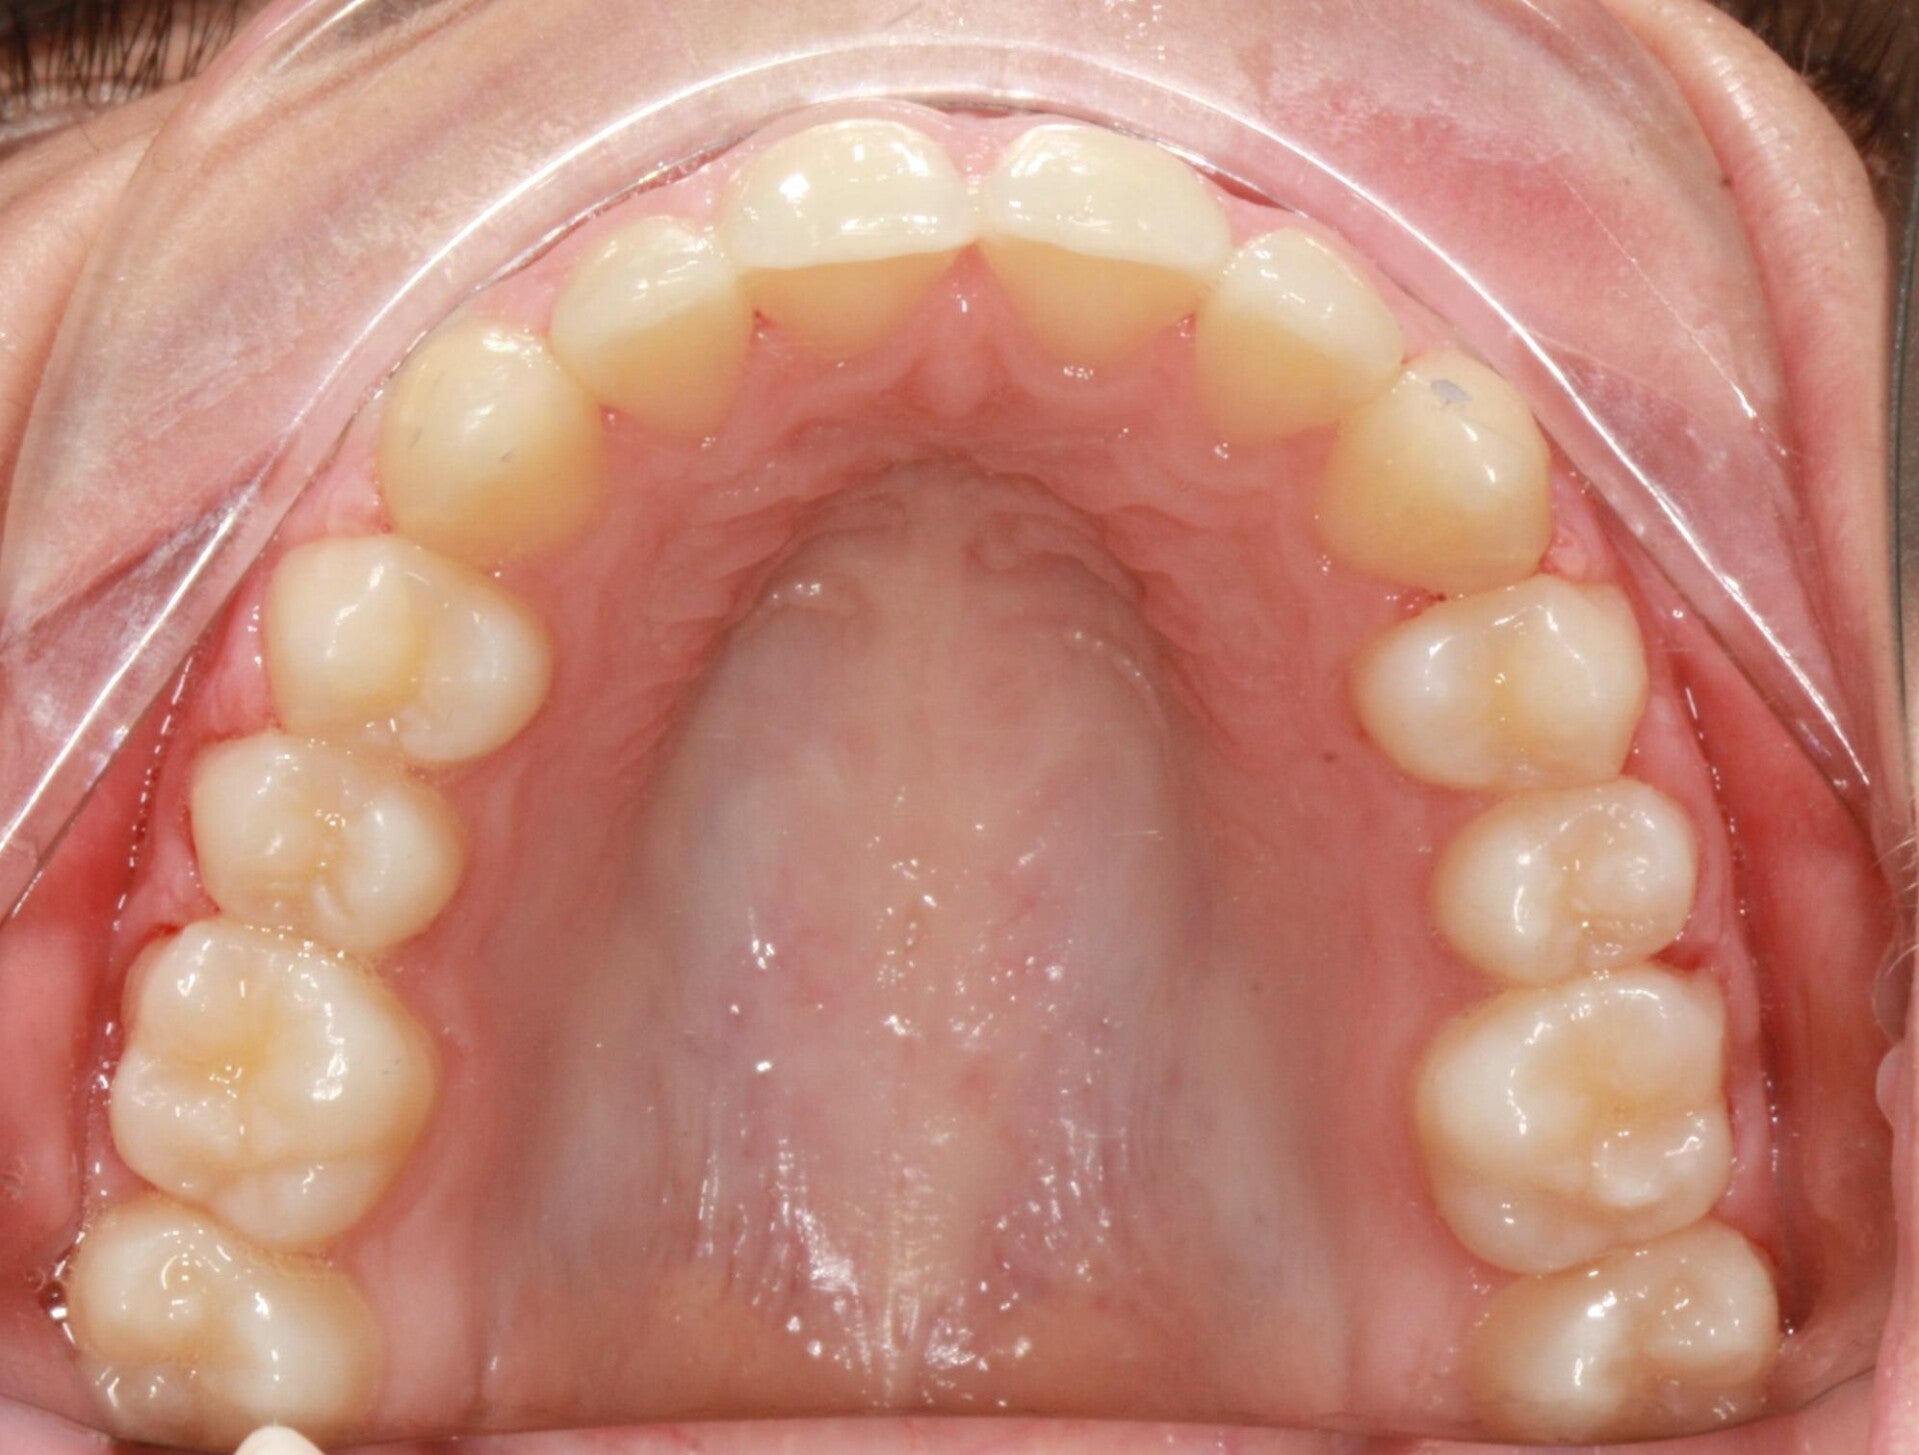

FOTO FINALI DOPO 24 MESI CIRCA DI TERAPA ORTODONTICA FISSA

Abbiamo appena portato a termine questo caso che presentava in arcata superiore il primo premolare di sinistra completamente fuori arcata sovrapposto al secondo premolare ed il canino ruotato.